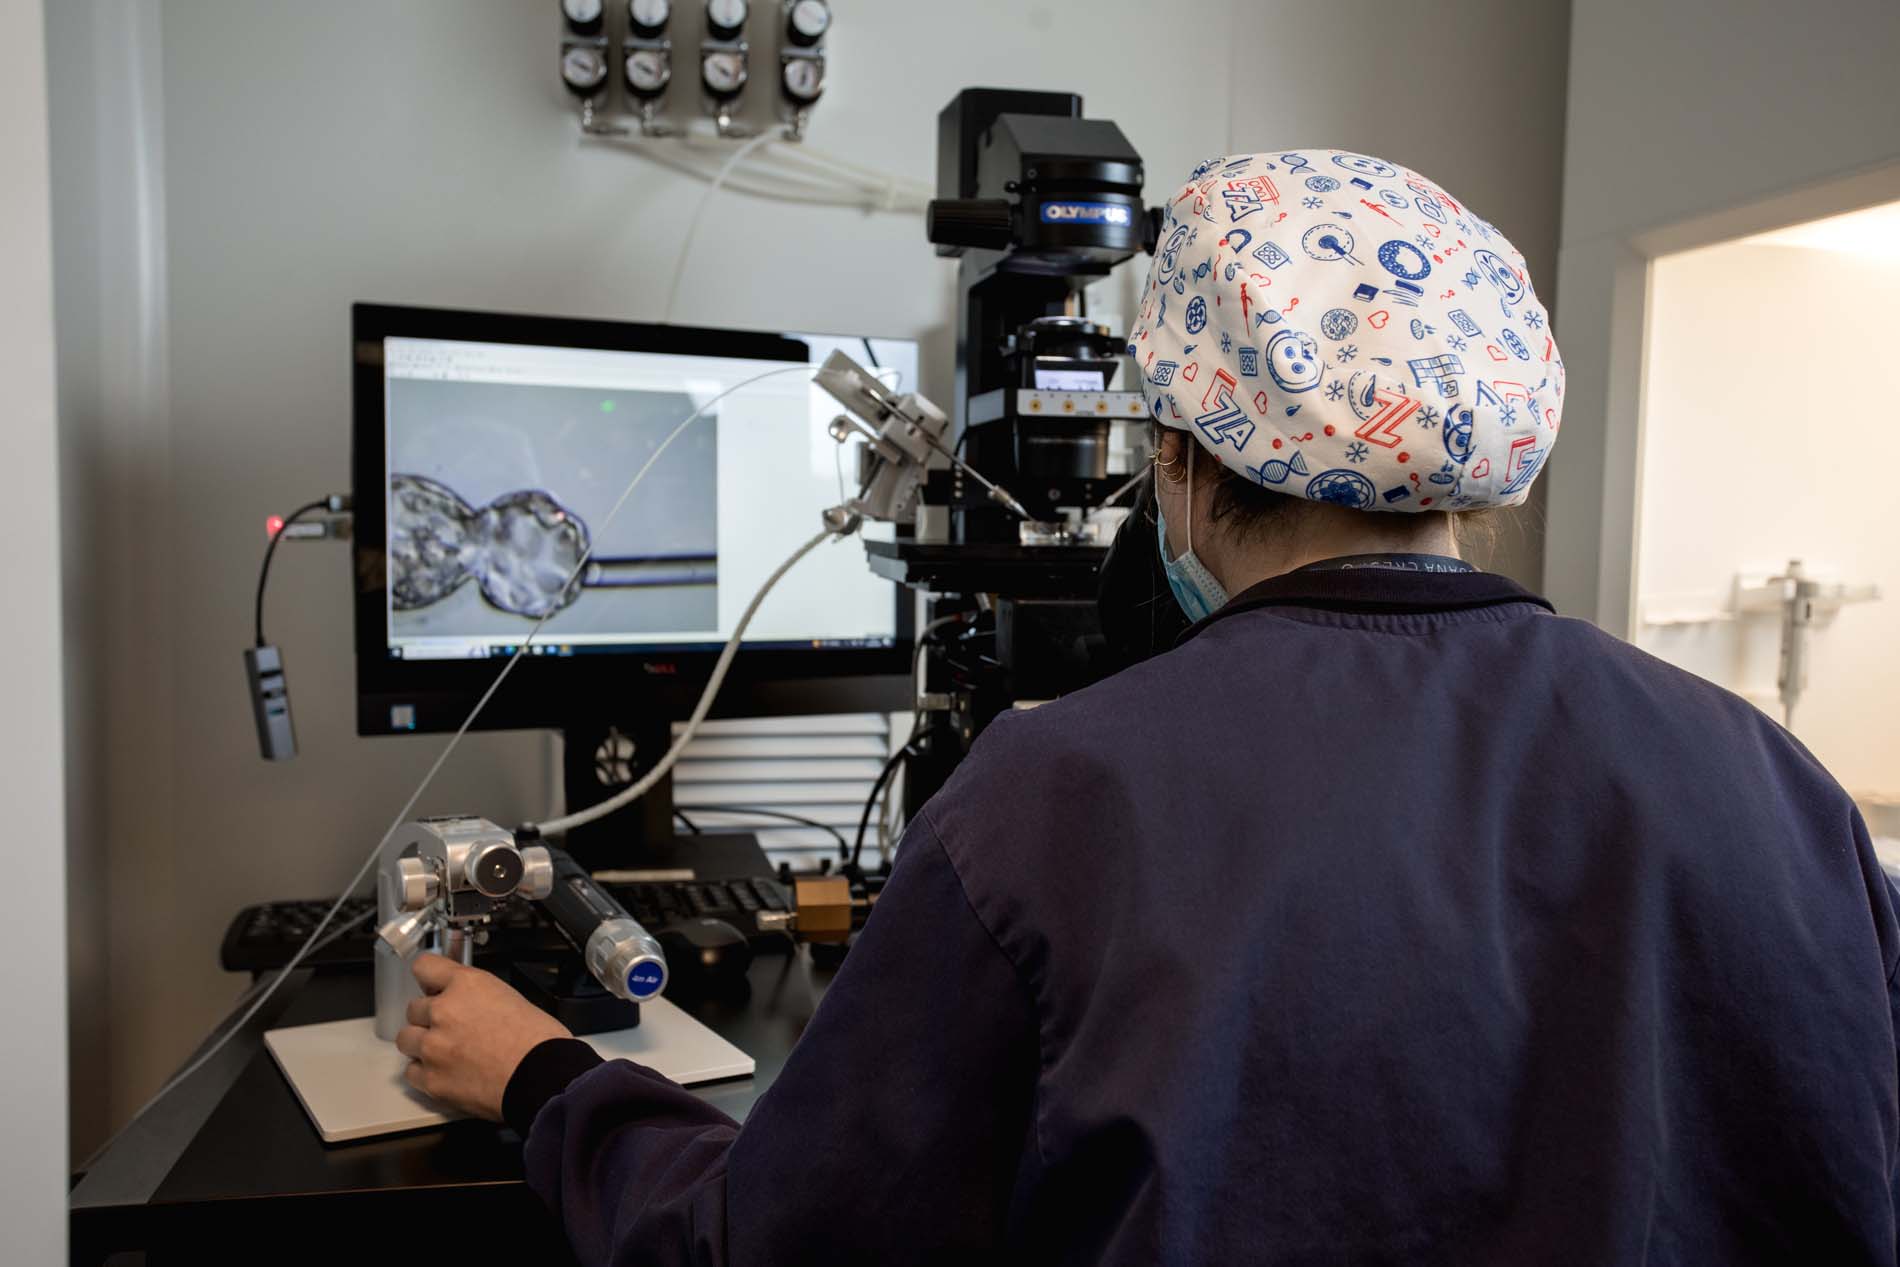

¿Por qué elegir una clínica especializada en alta complejidad reproductiva?

La búsqueda de un embarazo puede llegar a ser un proyecto largo y lleno de incertidumbre, sobre todo cuando el resultado no llega en el momento esperado. Muchas mujeres y […]